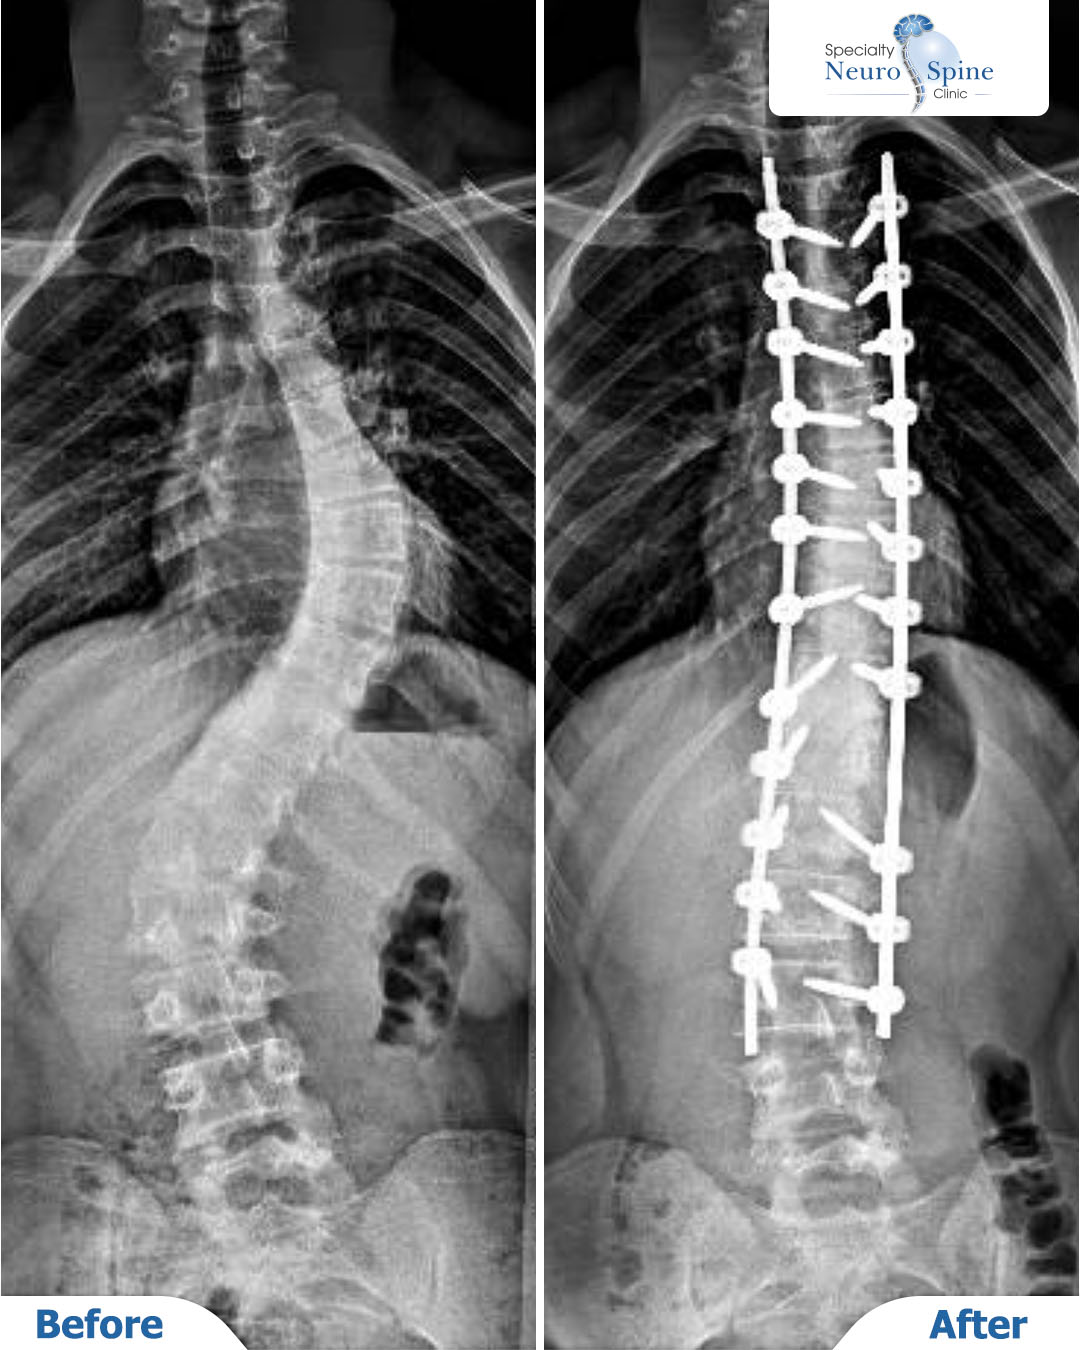

Before and after X-rays of our young patient, Abdullah, 18 years old, who had a severe spinal curvature extending from the fourth thoracic vertebra (T4) to the third lumbar vertebra (L3).

He underwent spinal fusion surgery performed by Dr. Firas Husban, resulting in excellent outcomes.